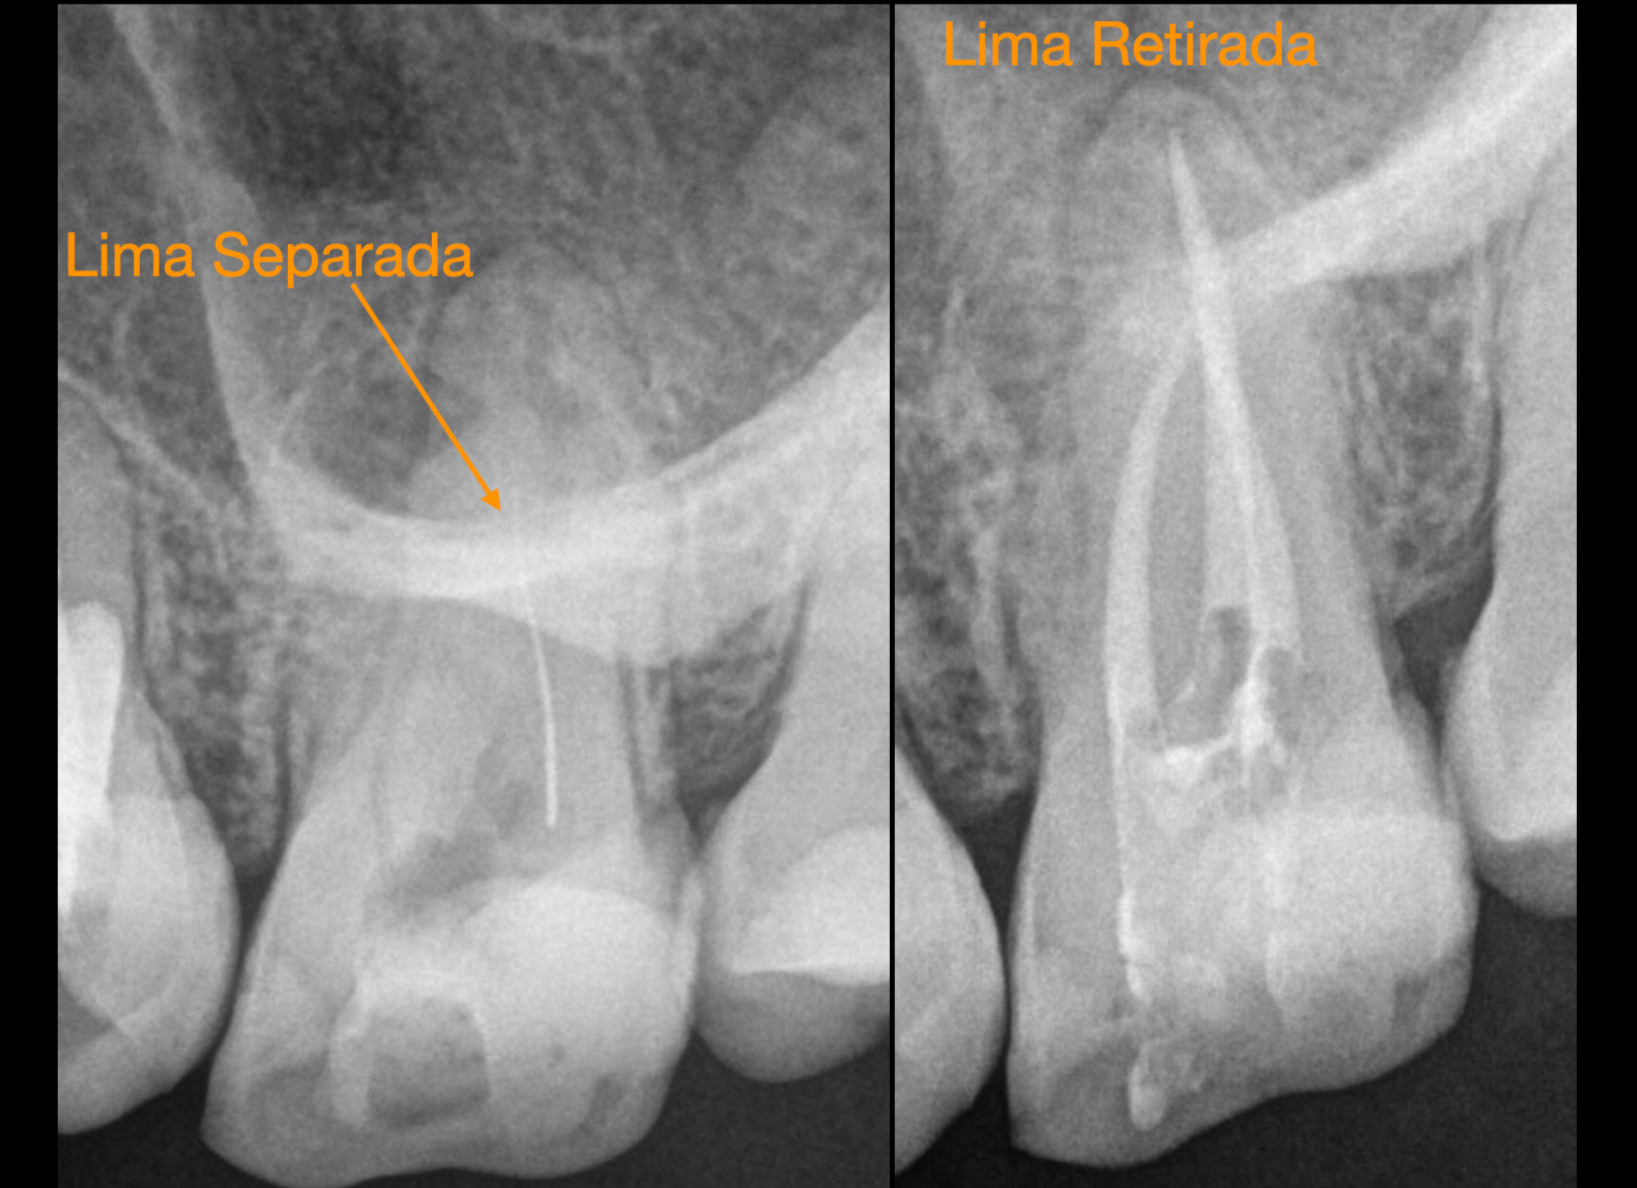

Limas Separadas

Gonzaga Zabalegui ofrece soluciones efectivas para los casos en los que una lima se ha separado durante un tratamiento de endodoncia. Con su experiencia, puede recuperar la lima y asegurar un tratamiento adecuado del diente afectado. Esto mejora significativamente el pronóstico a medio y largo plazo, favoreciendo la salud dental del paciente.